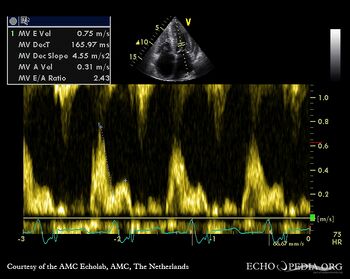

Pulsed-wave Doppler signal: restrictive pattern of mitral inflow